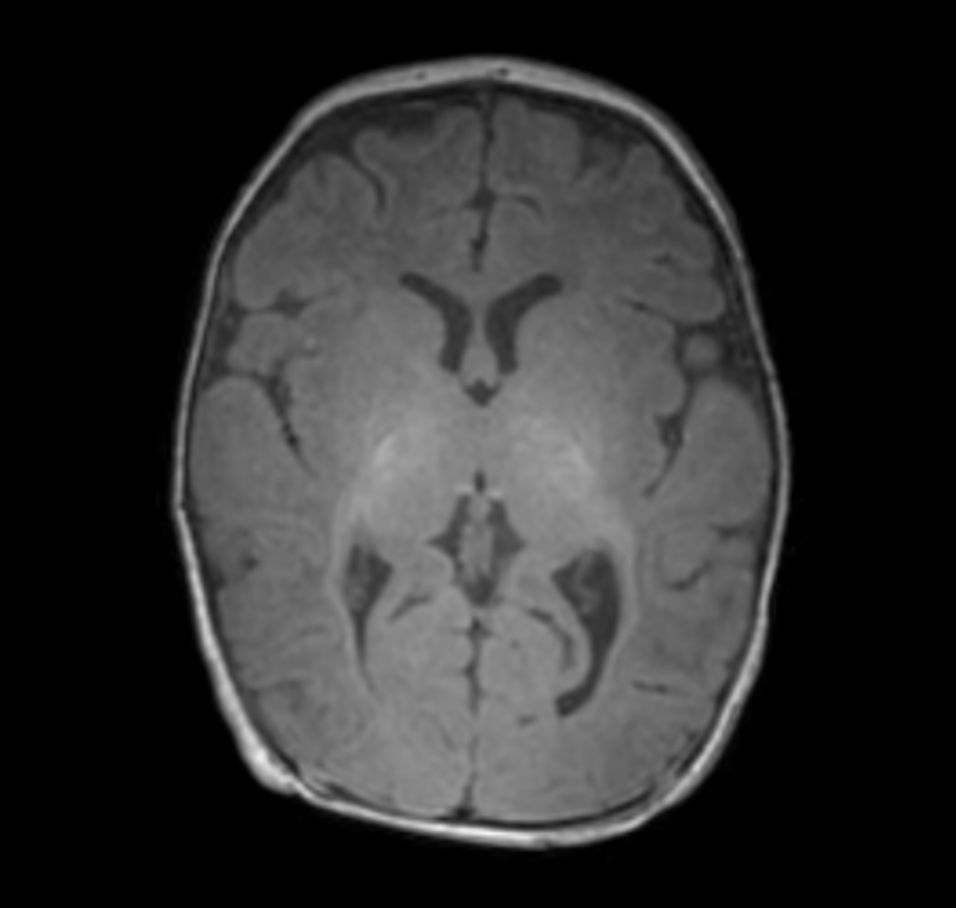

3D T1w TFE with ComforTone -  Axial reformat